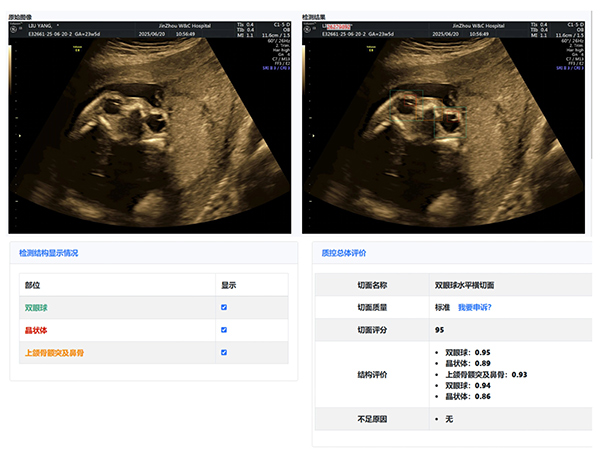

大赛汇聚了超声科全体医生,他们在产科超声领域各展所长。本次大赛引入了产前超声AI智慧云平台作为评分系统。

该平台利用先进的图像识别技术,对参赛的NT、I级、Ⅱ级、Ⅲ级产科超声图像进行精准分析与评分,确保了比赛的公正性与准确性,也体现了医院在医疗领域智能化、精准化的探索与进步。

经过激烈的角逐,年轻医生陈昱在NT产科超声图像评比中,凭借对NT精准的测量荣获第一名,展现出新生力量的专业风采;王斌医生在I级产科超声图像评比中,以精湛技术和对细节的精准把握摘得桂冠;刘芳医生的Ⅱ级产科超声图像作品,凭借清晰的图像质量和准确的诊断信息脱颖而出;Ⅲ级产科超声图像作品的评比竞争尤为激烈,李杭医生以微弱优势获得第一名。